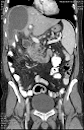

●従来に比べ、密度分解能を向上 全身・全領域対応の低ノイズ画像を提供可能となりました

●被ばく低減を実現

これまで広範囲のCT検査は、多列化が必須条件とされてきました。

多列化は画像への様々な悪影響や、被ばく増の問題もありましたが、今回のバージョンアップにより、列数に頼ることなく高画質、被ばく低減を実現いたしました。